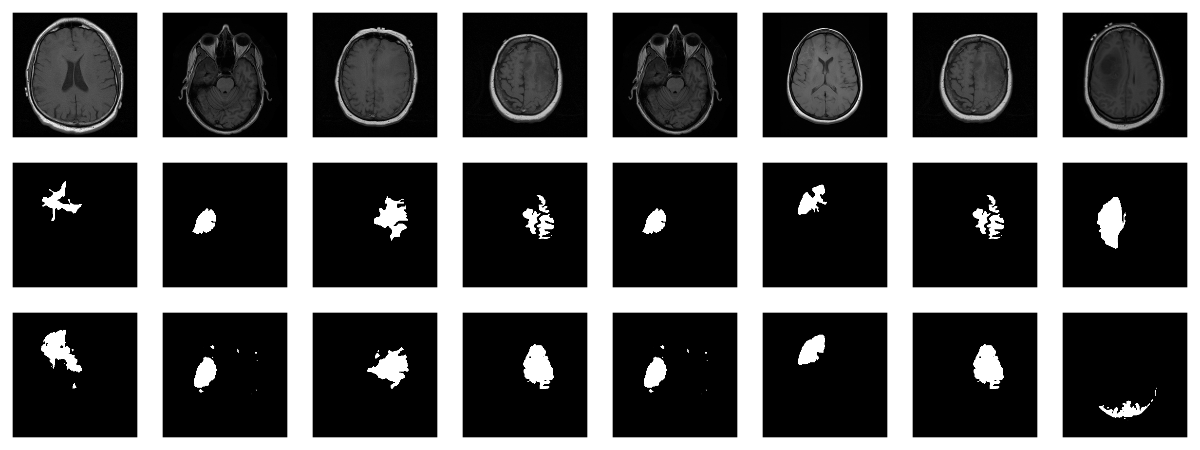

Now, since we don’t have a separate test set, we already know the average out-of-sample metrics; but in the end, what we care about are the generated masks. Let’s view some, displaying ground truth and MRI scans for comparison.

# without random sampling, we'd mainly see lesion-free patcheseval_ds<-brainseg_dataset(valid_dir,augmentation_params=NULL,random_sampling=TRUE)eval_dl<-dataloader(eval_ds,batch_size=8)batch<-eval_dl%>%dataloader_make_iter()%>%dataloader_next()par(mfcol=c(3,8),mar=c(0,1,0,1))for(iin1:8){img<-batch[[1]][i,..,drop=FALSE]inferred_mask<-model(img$to(device=device))true_mask<-batch[[2]][i,..,drop=FALSE]$to(device=device)bce<-nnf_binary_cross_entropy(inferred_mask,true_mask)$to(device="cpu")%>%as.numeric()dc<-calc_dice_loss(inferred_mask,true_mask)$to(device="cpu")%>%as.numeric()cat(sprintf("\nSample %d, bce: %3f, dice: %3f\n",i,bce,dc))inferred_mask<-inferred_mask$to(device="cpu")%>%as.array()%>%.[1,1,,]inferred_mask<-ifelse(inferred_mask>0.5,1,0)img[1,1,,]%>%as.array()%>%as.raster()%>%plot()true_mask$to(device="cpu")[1,1,,]%>%as.array()%>%as.raster()%>%plot()inferred_mask%>%as.raster()%>%plot()}

We also print the individual cross entropy and dice losses; relating those to the generated masks might yield useful information for model tuning.